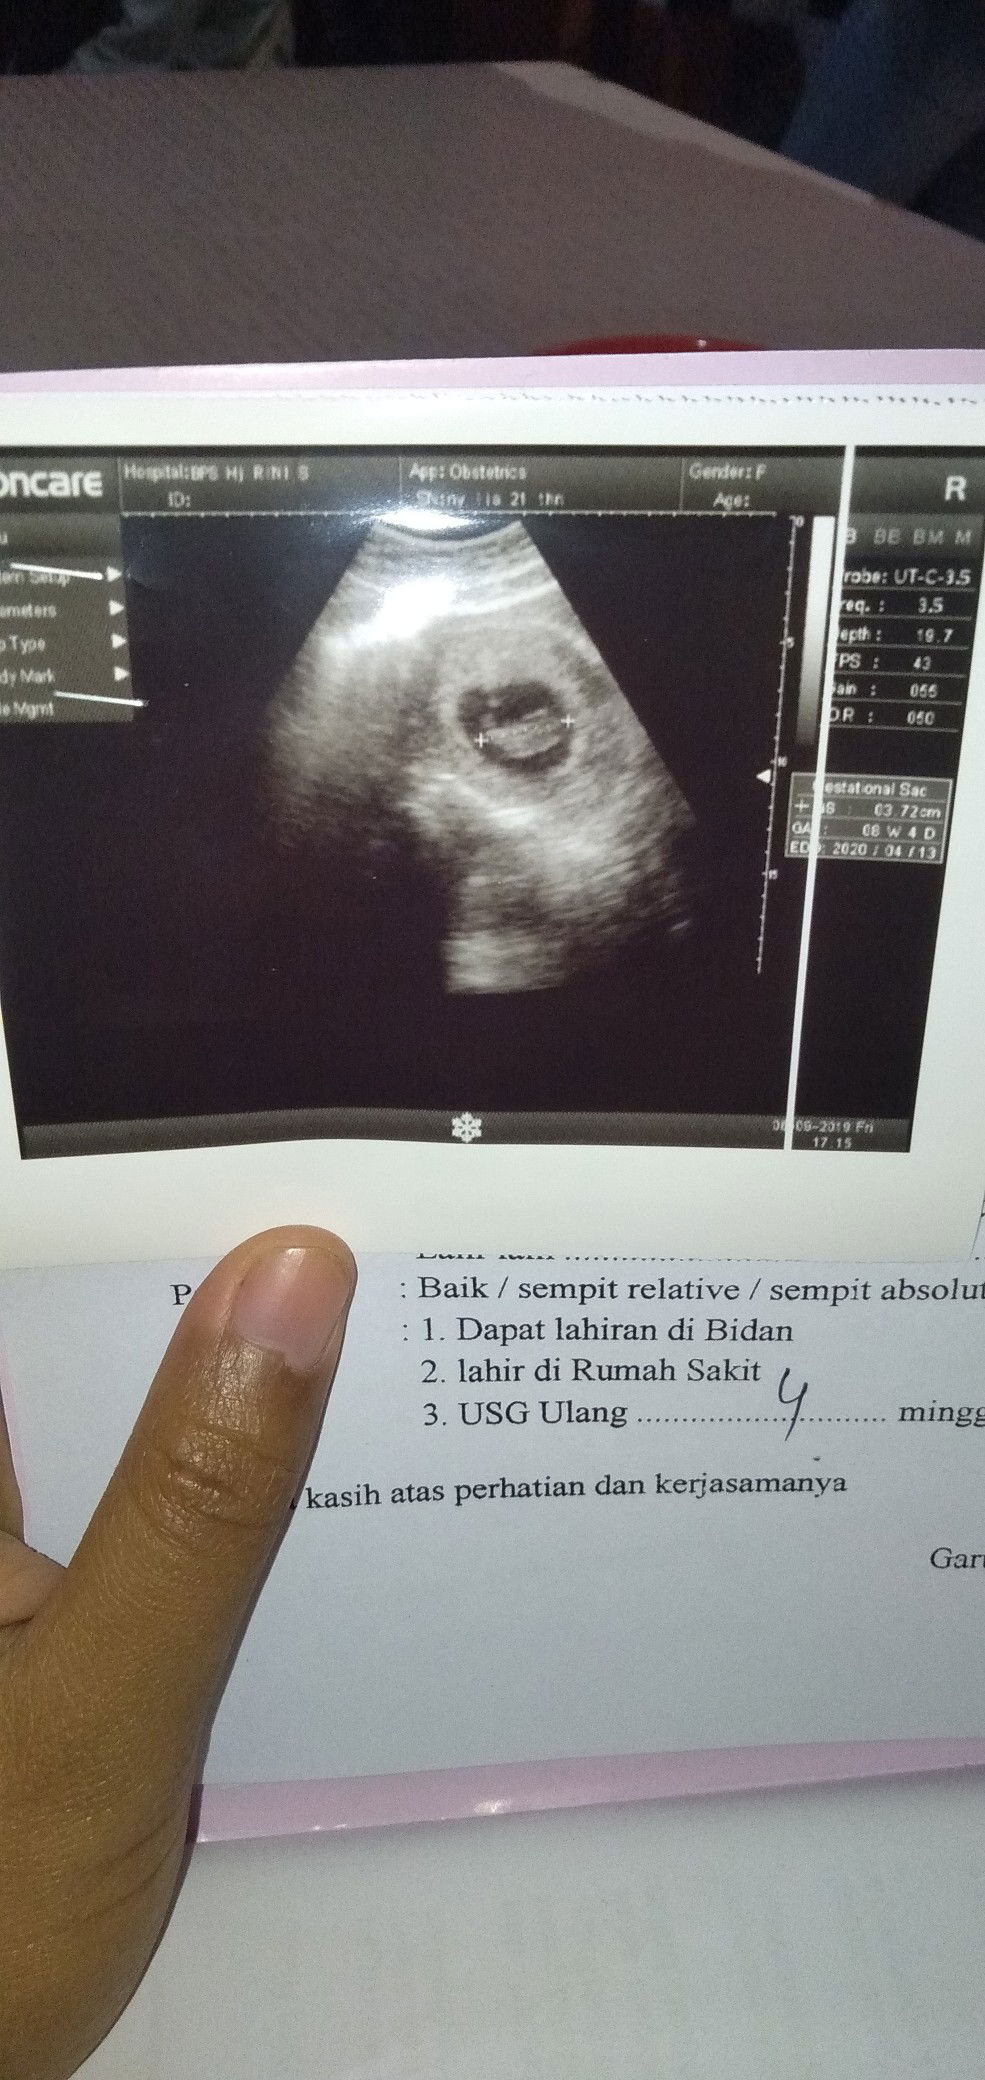

sedang mengandung

usg

Alhamdulillah . Hitungan saya udah 9 minggu tapi knpa ya beda